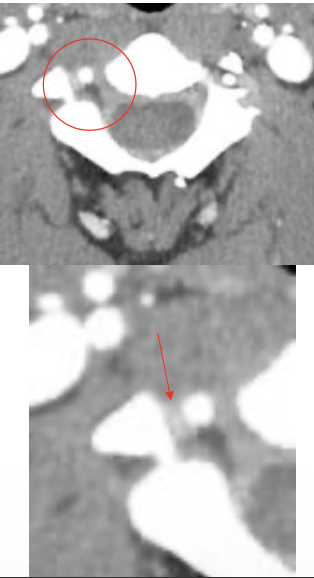

椎动脉

Vertebral artery

颈内静脉

Jugular vein

颈动脉

Carotid artery

蛛网膜下腔

Subarachnoid space

脊髓

Spinal cord